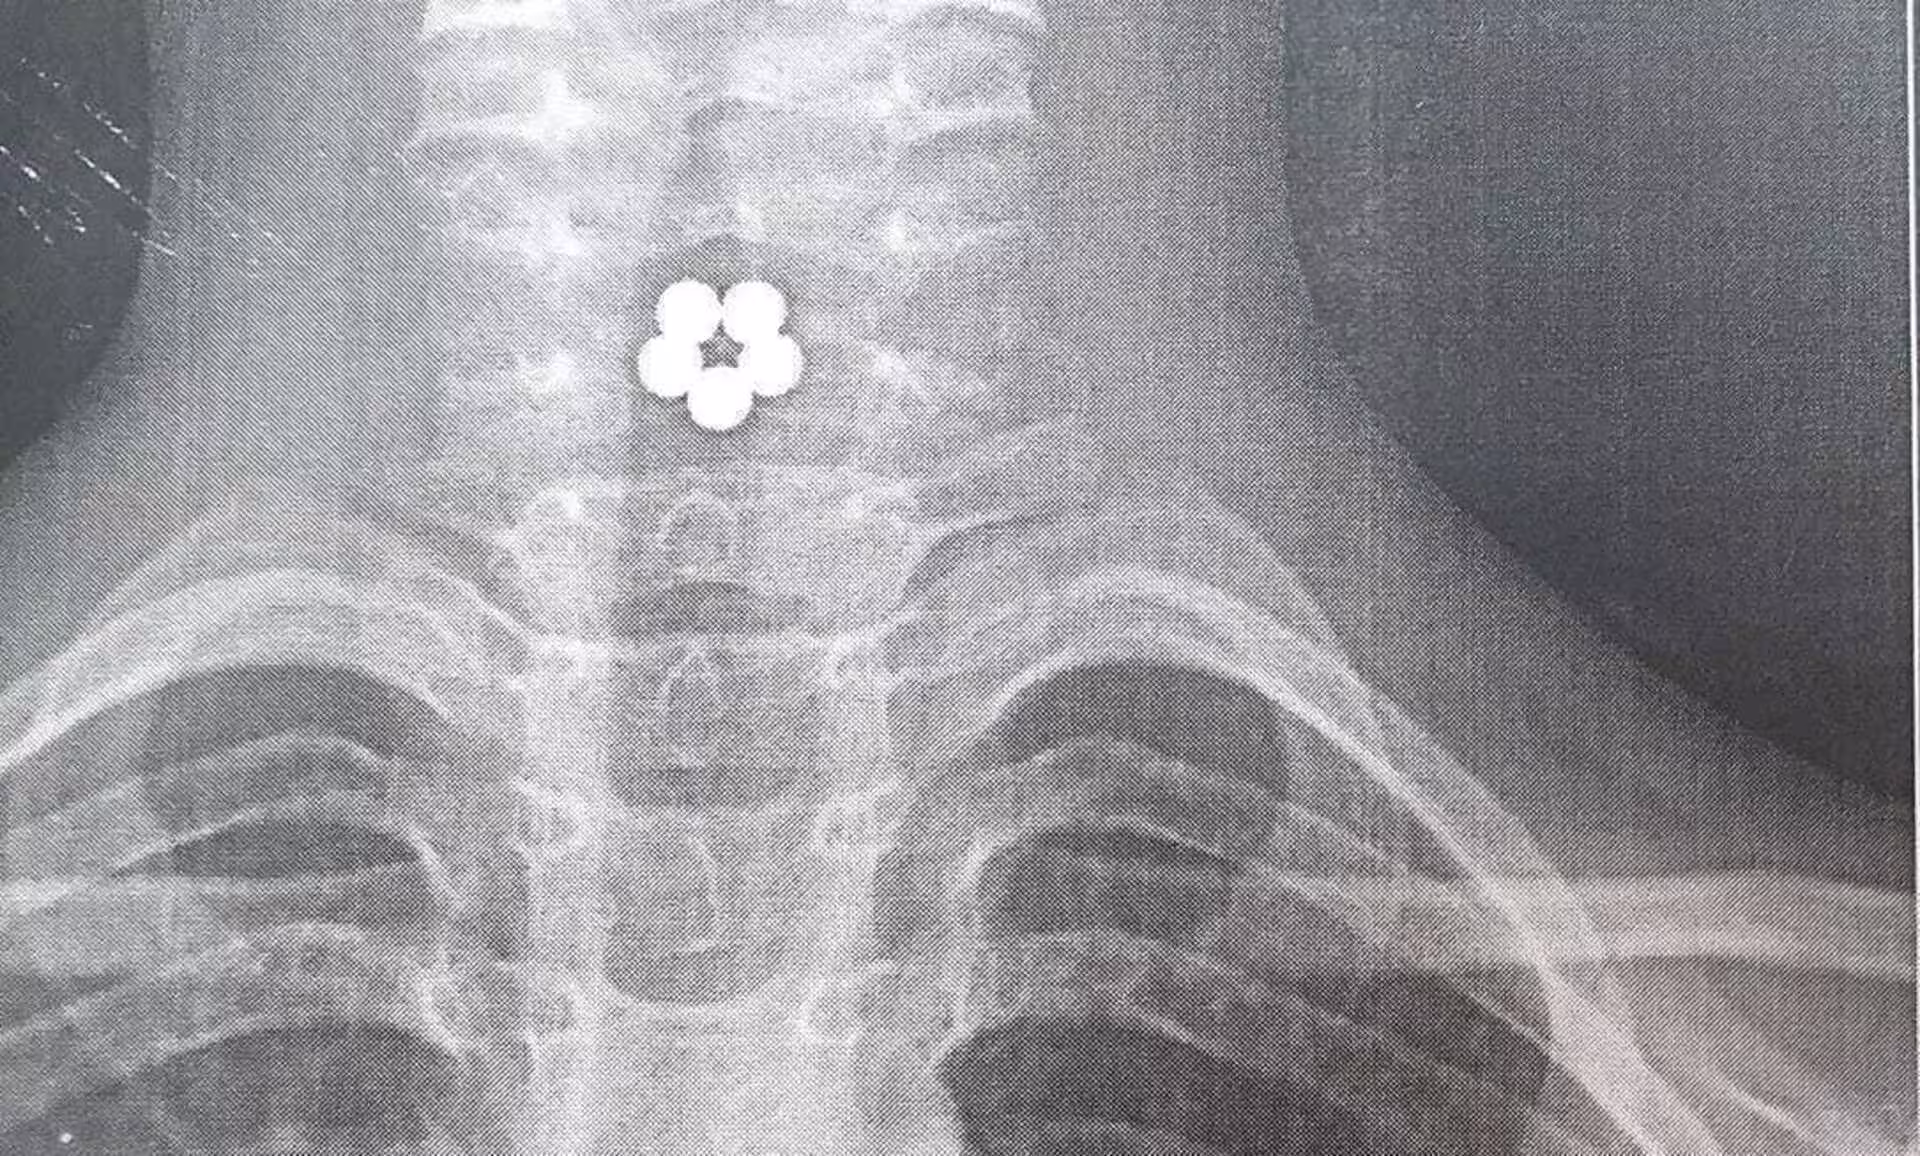

«Квіточка у стравоході у дитини. Ні, вона не справжня, а з магнітиків, які проковтнула семирічна дівчинка. Магнітики затрималися у стравоході і склалися в квіточку», — підписали фото рентгенівського знімку у лікарні.

У лікарні зазначили, що дякуючи швидкому реагуванні батьків та лікарів, магнітики не посунулися вниз до кишківника, інакше б наслідки могли бути набагато сумнішими.

«Коли дитину привезли в лікарню, їй невідкладно зробили рентген і, аби не допустити потрапляння магнітів у кишківник, що могло викликати перфорацію його стінок, хірурги одразу ж за допомогою сучасного інструментарію (щипці «Karl Storz», які лікарня отримала завдяки «Nova Ukraine» та Опікунська Рада ЛОДКЛ «Охматдит»), під контролем оптики, дістали магніти із стравоходу», — додали в лікарні.